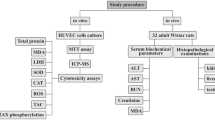

Herein, we assess the dose-dependent antioxidant efficacy of ultrafine spherical functionalized core–shell yttrium oxide nanoparticles (YNPs) with a mean size of 7–8 nm and modified with poly EGMP (ethylene glycol methacrylate phosphate) and N-Fluorescein Acrylamide. The antioxidant properties of these nanoparticles were investigated in three groups of Sprague–Dawley rats (10 per group) exposed to environmental stress daily for 1 week and one control group. Groups 2 and 3 were intravenously injected twice a week with YNPs at 0.3 and 0.5 mg at 2nd and 5th day of environmental stress exposure respectively. Different samples of blood and serum were collected from all experimental groups at end of the experiment to measure oxidative biomarkers such as total antioxidant capacity (TAC), hydroxyl radical antioxidant capacity (HORAC), oxygen radical antioxidant capacity (ORAC), malondialdehyde (MDA), and oxidants concentration as hydrogen peroxide (H2O2). The liver, brain, and spleen tissues were collected for fluorescence imaging and histopathological examination in addition to brain tissue examination by transmission electron microscope (TEM). Inductively coupled plasma-mass spectrometry (ICP-MS) was used to estimate YNPs translocation and concentration in tissues which is consecutively dependent on the dose of administration. Depending on all results, poly EGMP YNPs (poly EGMP yttrium oxide nanoparticles) can act as a potent direct antioxidant in a dose-dependent manner with good permeability through blood–brain barrier (BBB). Also, the neuroprotective effect of YNPs opening the door to a new therapeutic approach for modulating oxidative stress–related neural disorders.

Our study aimed to investigate the dose-dependent antioxidant efficacy of ultrafine functionalized core-shell yttrium oxide nanoparticles (YNPs) with poly EGMP and N-Fluorescein Acrylamide as functionalized monomer to help in tracking YNPs in vivo. Our study is the first innovative study that investigates the ability of functionalized core-shell YNPs to pass through BBB which was approved by TEM imaging in an environmentally stressed rats model to focus on a new therapeutic approach for control oxidative stress–related neural disorders.

For this study, three groups of male Sprague–Dawley rats (groups 1–3), each consisted of ten animals and one control group that weighed 150 g, aged 1 month old at the time of experimentation, were obtained from VACSERA laboratories (Egypt) and acclimated for 7 days after arrival before study in the lab animal house, Animal Health Research Institute (Giza, Egypt). Rodents in three groups were housed in an animal room and exposed daily to different temperature degrees (35–40 °C) for 6 h per day and (15–20 °C) for 6 h per night for 1 week. Control group was housed in an animal room at a controlled temperature (21–24 °C), humidity (30–45%), and light cycle (12 h light/dark).To detect the antioxidant efficacy of poly EGMP yttrium oxide NPs, experimental groups 2 and 3 were injected intravenously via tail vein with YNPs at 0.3 and 0.5 mg respectively which dispersed in 300 µl of sterilized water for injection twice a week at 2nd and 5th day of environmental stress exposure. Experimental group 1 is the group exposed to the same stress conditions but without any treatment. At the end of the experiment, blood and serum samples were collected through cardiac puncture; also tissue sections from the liver, brain, and spleen were collected under Isoflurane anesthesia effect for histopathological evaluation and tracking of YNPs internalization by fluorescence microscope and tissue concentration by ICP-MS; in addition, brain sections were imaged by TEM to investigate the ability of YNPs to pass through BBB.

Biochemical analysis of oxidative biomarkers

Oxidative stress was evaluated by measuring antioxidant activities as the total antioxidant capacity (TAC), hydroxyl radical antioxidant c(HORAC), and oxygen radical antioxidant capacity (ORAC), in addition oxidative byproduct level as malondialdehyde (MDA) and oxidants concentration as hydrogen peroxide (H2O2).

Determination of YNPs internalization and tissue concentration

Histopathological studies

TEM imaging of YNPs in brain tissues

Statistical analysis